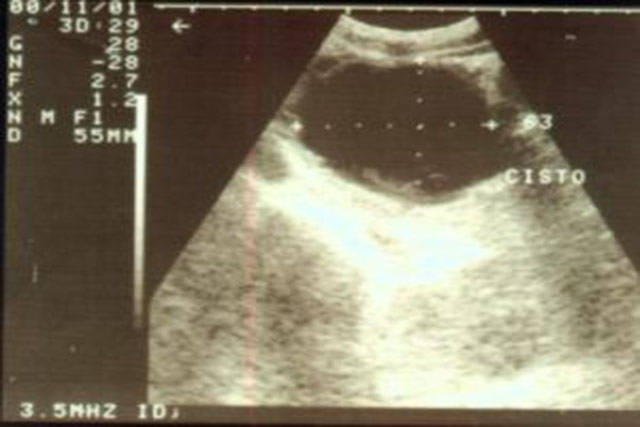

Ultrasonografia de pâncreas evidênciando

grande pseudocisto.